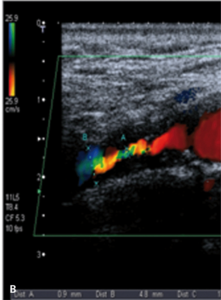

Badanie ultrasonograficzne doppler duplex tętnic szyjnych i ocena koła Willisa

Badaniem ultrasonograficznym można uwidocznić zwężenie i ocenić jego morfologię.

Zmiany hipoechogeniczne to zmiany częściej lipidowe lub skrzepliny, zmiany izoechogeniczne to zmiany włókniste, a zmiany hiperechogeniczne zawierają zwapnienia.

Zmiany hipoechogeniczne (skrzeplina, lipidowa) są związane z dużym ryzykiem IS zarówno u chorych dotychczas bezobjawowych, jak i w trakcie CAS czy endarterektomii (carotid endarterectomy, CEA), bo łatwo je uruchomić i rozkruszyć, powodując zatory do tętnic mózgowych [18].